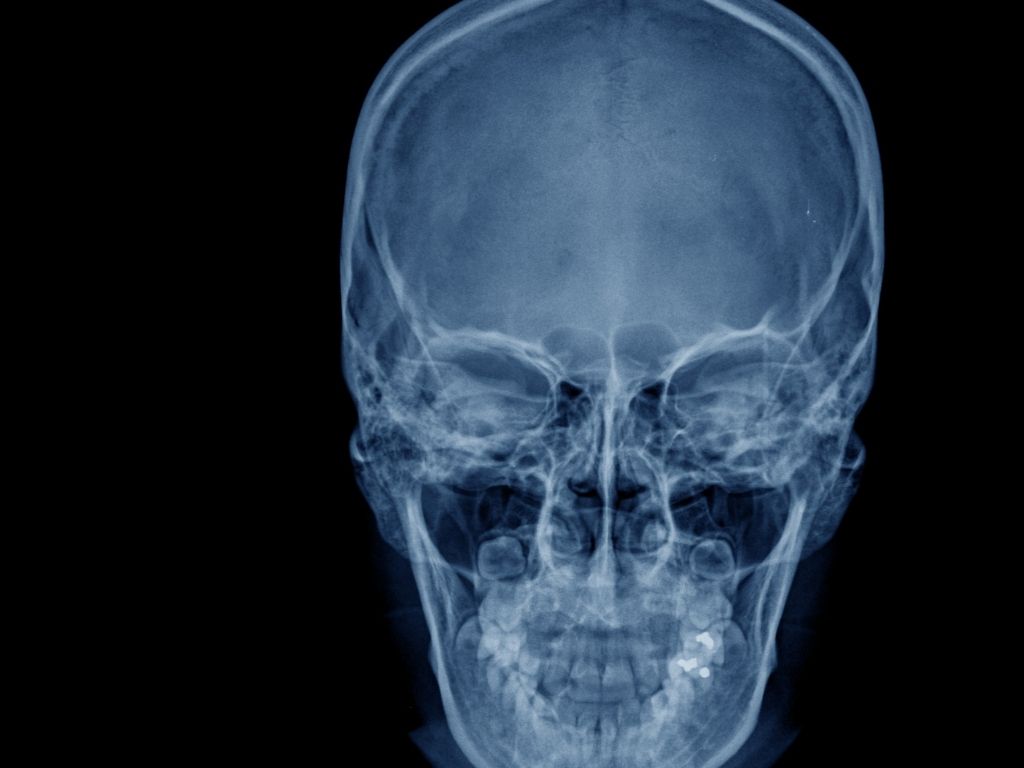

Травми носа трапляються частіше, ніж здається. Незручний рух, випадковий удар, спортивна травма чи побутова ситуація – і вже з’являється набряк, біль, утруднене носове дихання. Візуально оцінити стан кісток не завжди можливо: перелом може бути без вираженої деформації, а зміщення – мінімальним, але достатнім, щоб вплинути на дихання або форму носа в майбутньому.

Саме тому рентген кісток носа залишається базовим і обов’язковим методом діагностики. Він дає чітку відповідь: є перелом чи ні, чи є зміщення фрагментів, наскільки серйозне ушкодження та чи потрібне втручання лікаря.

Що показує рентген кісток носа

Дослідження дозволяє виявити:

переломи кісток носа – прямі, осколкові, втиснуті;

зміщення кісткових фрагментів;

тріщини, які зовні можуть бути непомітними;

стан носових кісток після ударів або падінь;

наслідки старих травм, які впливають на дихання або функцію перегородки.